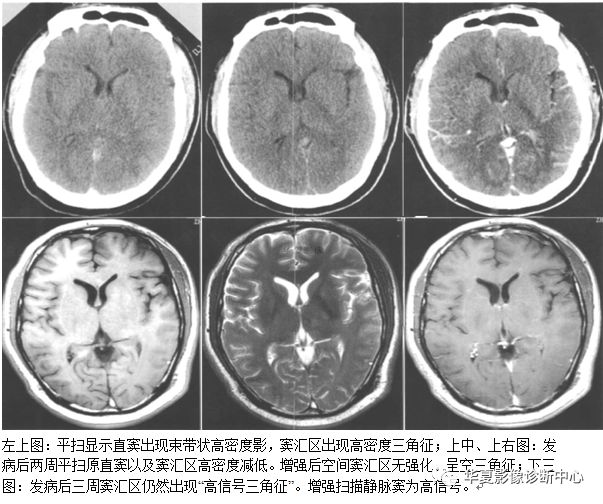

十三、空三角征:

在CT或MRI增强图像上,在多个连续的横断CT或MRI图像上表现为上矢状窦三角形增强或高密度区域内出现相对低密度区。空三角征为矢状窦血栓形成时颅脑增强CT或MRI的常见征象,出现率约为35%,表现为强化的三角形环即中心低信号周边为三角形高信号,位于上矢状窦区。矢状窦邻近有血管丛,为血栓形成后的侧支循环。目前对该征病理生理的解释并不一致,包括以下假说:1)静脉窦内血栓再通。2)栓子机化。3)血脑屏障破坏。4)硬膜外和硬膜侧支静脉的扩张。有认为最合理的解释为硬膜血管的强化,为所在区域的血管网(硬膜海绵间隙)和脑膜静脉属支的强化,中心低密度为栓子。国外学者认为血栓形成的主要原因有3个:1)血管易于血栓形成,包括原发性和遗传性疾病。最常见为继发性凝血酶原激活如妊娠;血液或系统性疾病如红细胞增生症、系统性红斑狼疮、恶性肿瘤、脱水导致血液浓缩,药物如避孕药或化疗药如L一天门冬酸胺酶。2)血流障碍如肿瘤、心衰、动静脉痊。3)静脉窦壁的炎症、感染、纤维化或损伤,如:静脉窦炎、外耳炎、乳腺炎和创伤。l/4的病人查不到原因。矢状窦血栓形成的临床表现有头痛、视乳头水肿等。急性脑静脉窦血栓形成往往存在比较典型的表现,可见上矢状窦区三角形以及横窦区条索状高密度影,是脑静脉窦内新形成血栓病变早期的直接折射;临床上虽然脑硬膜窦血栓的发病率较高,不过单纯大脑浅静脉及深静脉部位的血栓形成较少;CT增强显示空三角征或条状充盈缺损,特征明显,对急性和亚急性患者有重要意义。CT平扫亦可显示由于静脉淤血、静脉性脑梗死以及脑脊液重吸收障碍引起的病理征象,如对称或弥漫性脑肿胀、多灶性脑出血等。

MRI平扫对本病较为敏感,可显示不同时期血栓的信号,而正常静脉窦的留空信号则消失。急性期T1WI为等信号,与留空信号较为接近,T2WI为低信号,由于信号特征较不明显,因此MRI不易诊断;亚急性期T1WI、T2WI均为明显高信号,容易确诊;慢性期各脉冲序列血栓信号减低,常常出现假阳性。但是可通过与CVST引发的脑水肿、脑梗死、脑积水等间接征象相结合,以辅助诊断。